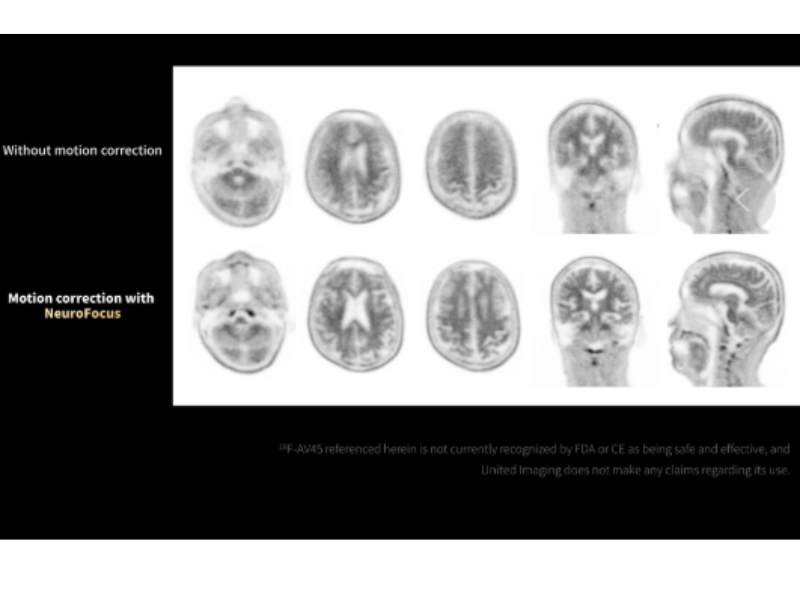

NeuroFocus mitigates head motion artifacts in 18F-AV45 imaging.